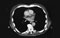

CT of the great vessels CT of the pulmonary veins 11. Examine the great vessels and gross features of the heart. (Play movie; View images: N 196, 206, 212, 214, 215, 231, 241, TG 4-15, 4-19, 4-22, 4-29, 4-35, 4-36)

Now relate all the great vessels (superior vena cava, pulmonary trunk and aorta) to one another and to the trachea.

CT of the trachea Observe the attachment of the pericardial sac to the diaphragm. Note the serous layer reflecting across the surface of the diaphragm. Review the total extent of the fibrous layer. Observe the serous layer; define its parietal and visceral (epicardium) parts. Note that the two become continuous (lines of reflection) at the great arteries (aorta and pulmonary trunk) and great veins (superior and inferior venae cavae; pulmonary veins). Explore the pericardial cavity. Insert your index finger behind the pulmonary trunk and ascending aorta, i.e., into the transverse pericardial sinus. Lift the apex of the heart and slip two or three fingers behind the heart into the oblique pericardial sinus. This sinus is formed by the reflection of the serous pericardium around the inferior vena cava and the right and left pulmonary veins.